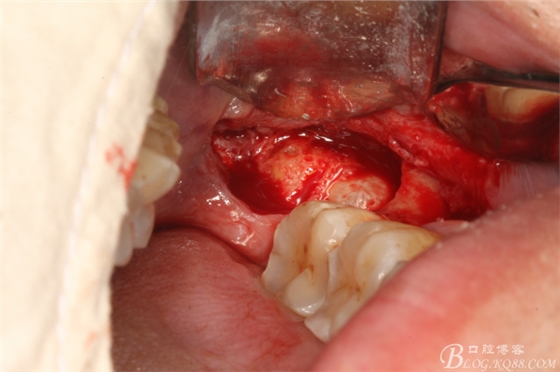

圖4.橫斷牙根和牙冠

圖5.首先取出牙根

圖7.然后取出牙冠

圖8. 取出后的38拔牙窩